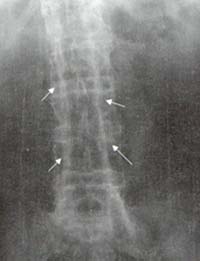

Osteofito marginal: corresponde a un sobrecrecimiento óseo que contiene hueso laminar y medular secundario a una herniación discal. A diferencia del sindesmofito marginal en los osteofitos la calcificación se origina del cuerpo vertebral y se dispone inicialmente en forma horizontal y más tardíamente en forma de gancho (Figura 3)

Figura 3. Radiografía frontal de columna lumbar Osteofitos a lo largo

de la columna lumbar, en forma de gancho (Flechas) que hacen puentes entre

un cuerpo vertebral y otro.